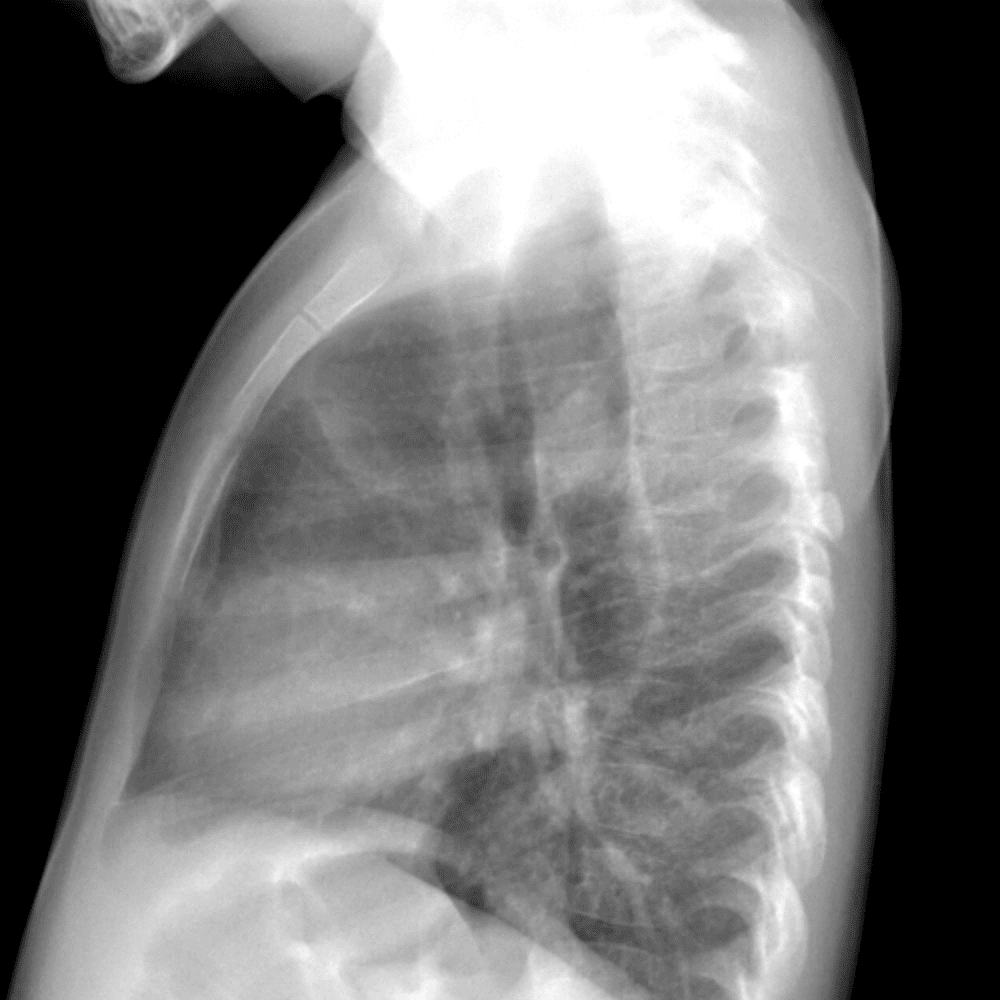

Peds Chest

Practice

Simulates call by including subtle or difficult cases and some normals.

50 cases